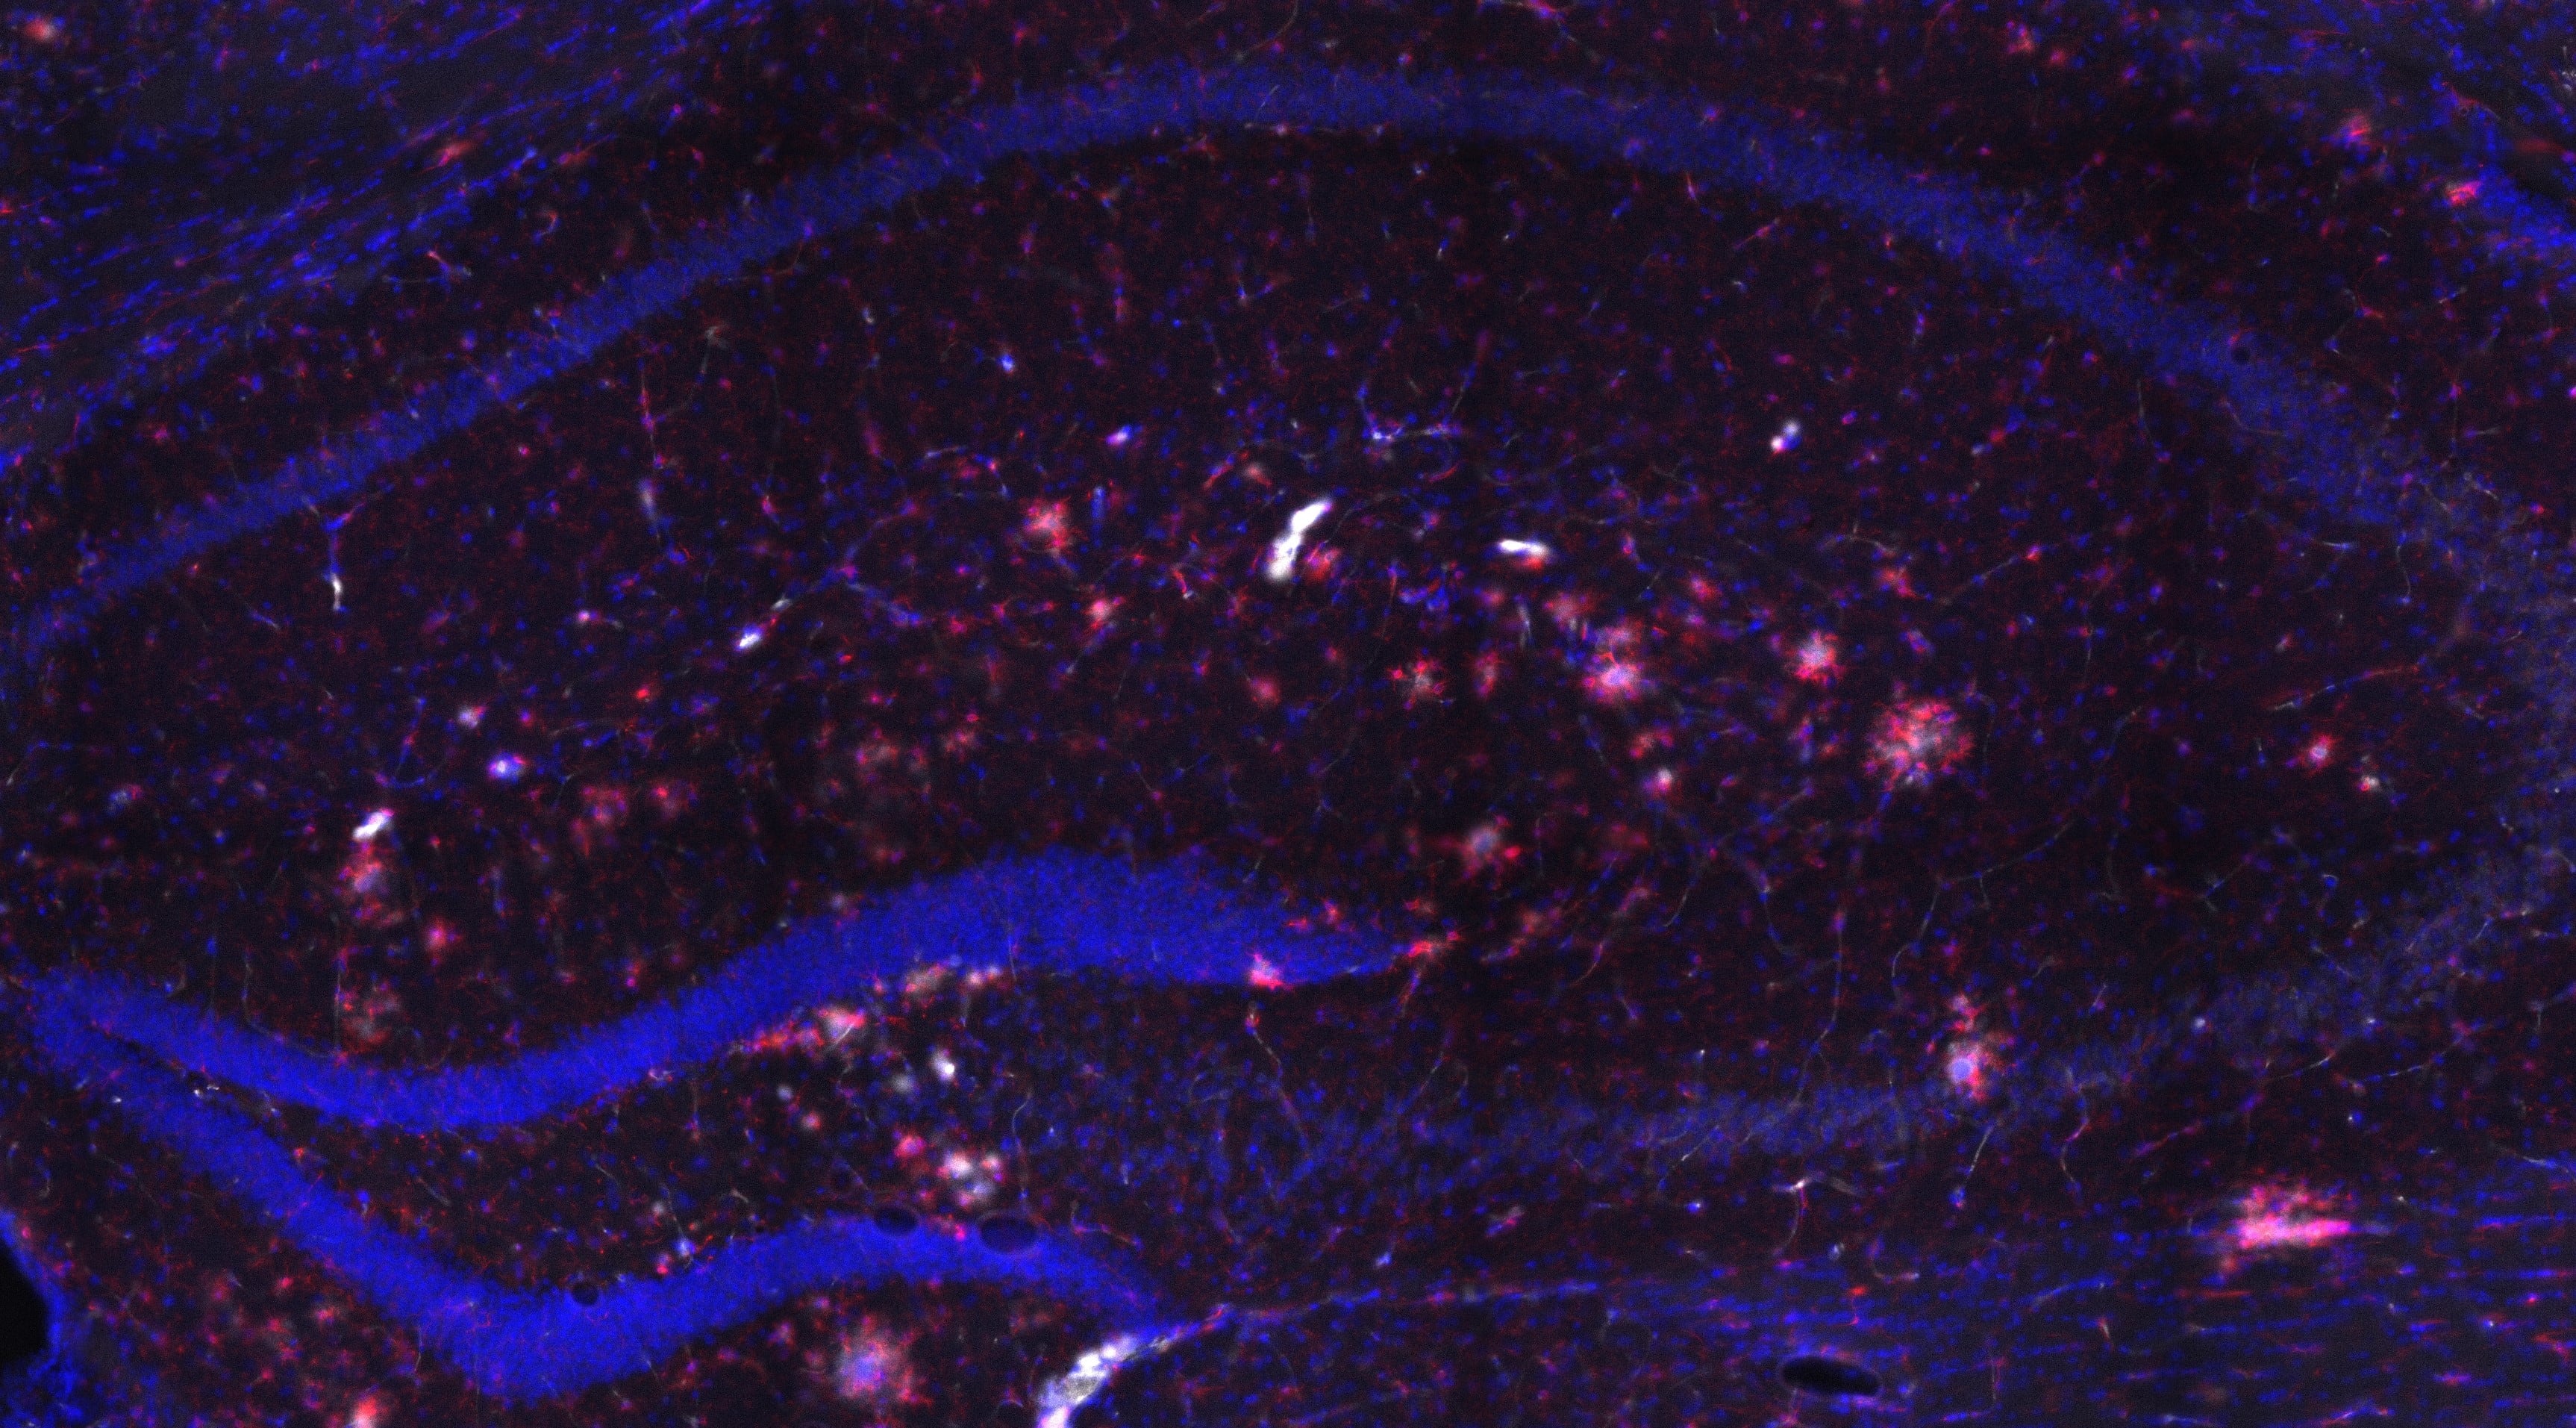

En los últimos años se ha descubierto que el sistema inflamatorio tiene un papel importante en las fases muy tempranas del alzhéimer. Sin embargo, estudiar la microglía en vivo, de forma no invasiva, es un proceso complicado. El laboratorio Biomarcadores de Imaging Traslacional, dirigido por Silvia De Santis en el Instituto de Neurociencias, centro mixto del Consejo Superior de Investigaciones Científicas y la Universidad Miguel Hernández de Elche, ha desarrollado una técnica que permite monitorizar la microglía para llevar a cabo este estudio. Esta propuesta de investigación ha sido una de las dos galardonadas, de entre 40 solicitudes, por la Fundación Pasqual Maragall, que ha anunciado hoy los dos ganadores de la convocatoria.

Las células de la microglía son células inmunitarias que se encuentran en el cerebro y la médula espinal, cuya función principal es actuar como la primera línea de defensa del sistema inmunológico en el cerebro. “Actualmente, la microglía ha cobrado un papel fundamental en la investigación del álzhéimer porque estas células actúan para contener el daño de la patología, pero su activación prolongada puede agravar la degeneración cognitiva. Esta dualidad hace que el estudio que planteamos sea clave para entender mejor la evolución de la enfermedad”, explica De Santis.

El laboratorio que lidera la investigadora en el Instituto de Neurociencias de la UMH ha desarrollado una nueva técnica de imagen cerebral no invasiva, basada en imagen por resonancia magnética, que permite monitorizar la microglía. El objetivo del proyecto es aplicar esta tecnología en un modelo animal de la enfermedad de Alzheimer y, posteriormente, adaptarla a pacientes humanos.

Además, se utilizará inteligencia artificial para mejorar la interpretación de imágenes previas, aumentando su resolución y permitiendo analizar el estado de activación de la microglía en imágenes ya adquiridas. “La inflamación cerebral mediada por microglia es uno de los factores clave en las primeras fases del alzhéimer. Este trabajo nos permitirá obtener una mejor comprensión de su papel en la progresión de la enfermedad y podría abrir la puerta a nuevas terapias”, señala De Santis.